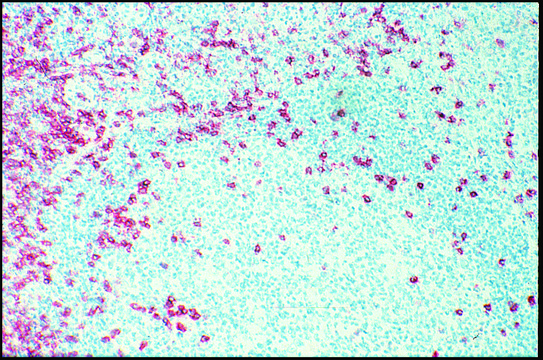

Recognizes the CD8 human T cytotoxic/suppressor lymphocyte cell surface glycoprotein. Approximately 90% of thymocytes are stained in suspension. In thymus sections, both cortical and medullary thymocytes are stained. A subset of NK cells express this antigen weakly. The epitope recognized by this clone is sensitive to routine formalin fixation and paraffin embedding.